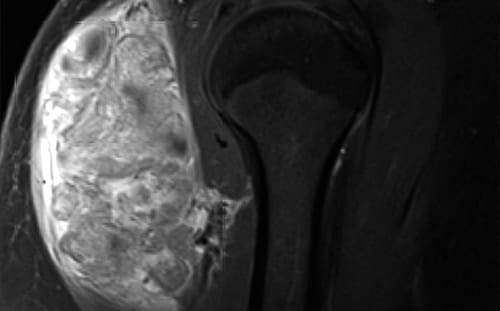

X-ray image of Shoulder Sarcoma

Soft Tissue Sarcoma: Orthopedic oncologists at University Hospitals collaborate with other specialists to treat benign and malignant soft tissue tumors of the extremities, trunk and pelvis.